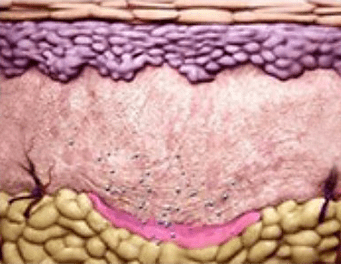

PLA 성분이 분해 되면서

콜라겐 등의

신생조직 생성을 촉진 -

약 6주 후 부터

피부복원 효과 확인 가능